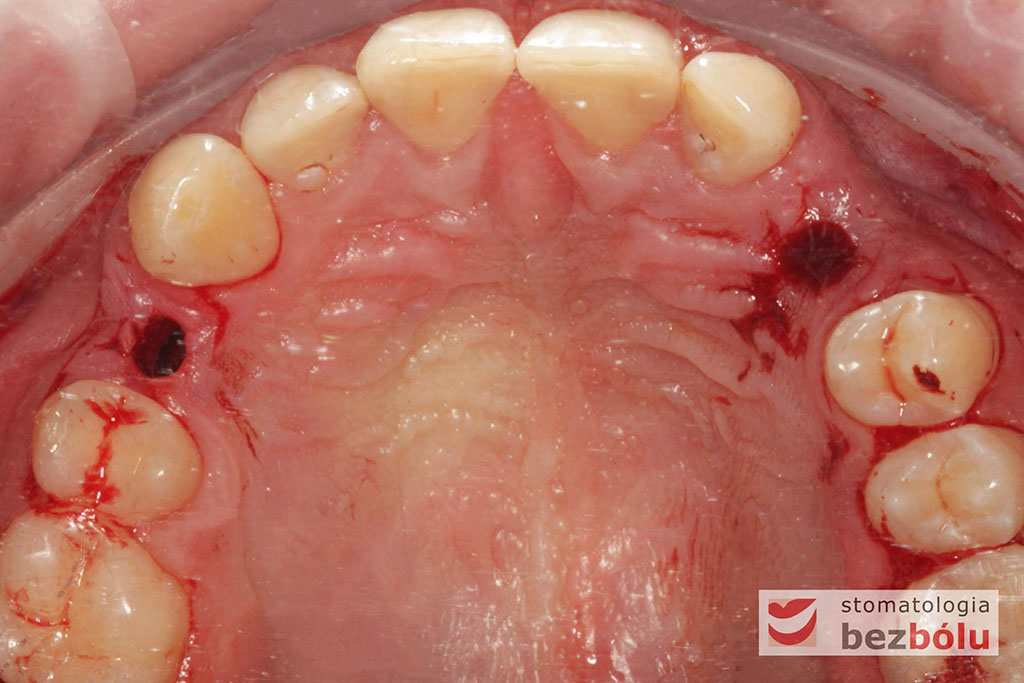

Procedurę chirurgiczną rozpoczęto od sprawdzenia przylegania szablonów do zębów pacjenta oraz znieczulenia miejscowego. W kolejnym kroku, przy pomocy specjalnie przeznaczonego do tego celu zestawu wierteł, wypreparowano krążki dziąsła punktowo odsłaniające kość a następnie poprzez tuleje prowadzące, z najwyższą precyzją, opracowano łoże implantu. Kulminacyjny moment zabiegu, czyli wprowadzenie wszczepów MIS C1 również odbyło się poprzez szablon, gwarantując precyzyjną lokalizację implantów. Zwieńczeniem całej procedury było przyszycie uprzednio wypreparowanych krążków śluzówkowo-okostnowych. Tuż po zabiegu, celem weryfikacji poprawnej pozycji implantów, wykonano zdjęcie ortopantomograficzne. Podczas wizyt kontrolnych, pacjent nie skarżył się na żadne dolegliwości bólowe, nie wystąpił obrzęk, a zreponowane we właściwych miejscach fragmenty dziąsła nie wykazywały oznak martwicy, co świadczyło o ich ponownym ukrwieniu i wgojeniu się. Wszystkie te przesłanki jasno wskazują na skuteczność zastosowania techniki komputerowej nawigacji w implantologii.